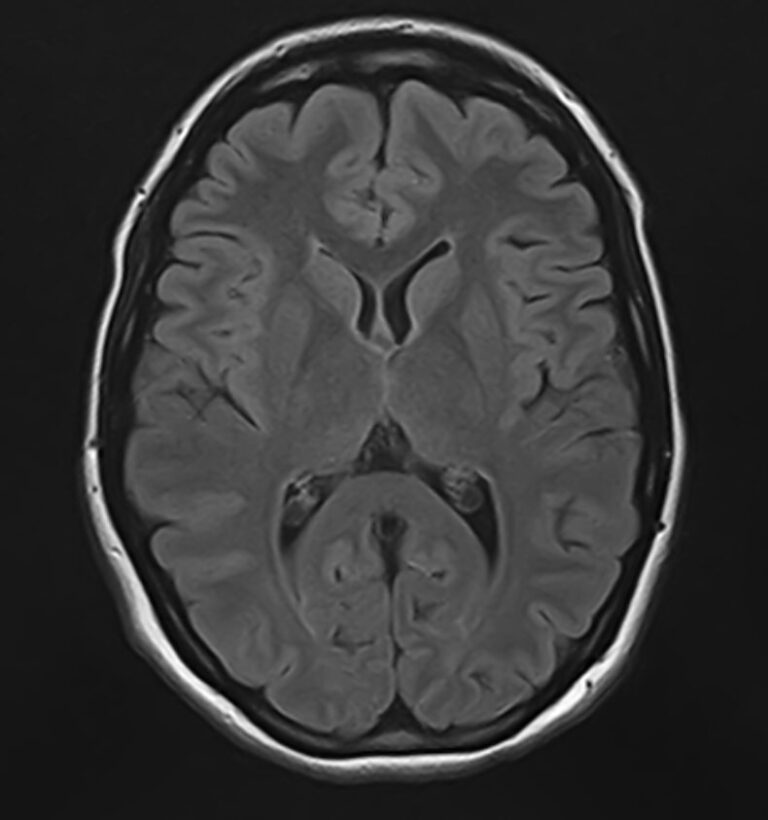

В клинике «Доступная медицина» можно пройти комплексное обследование, включающее в себя два протокола сканирования близко расположенных друг от друга анатомических областей – шейного отдела позвоночника и головного мозга.

Сканирование проводится на современном высокопольном магнитно-резонансном томографе закрытого типа TOSHIBA VANTAGE TITAN 1,5 Тесла, который делает послойные срезы в разных плоскостях с шагом от 1 мм и на основе полученных данных создает трехмерные изображения превосходного качества. Метод исследования позволяет в мельчайших подробностях визуализировать состояние всех структур головного мозга и шейного отдела позвоночника, что дает возможность выявлять патологические изменения на ранних стадиях и назначать своевременное лечение.